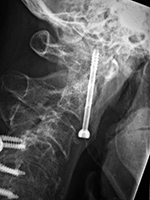

Odontoid screw (nail) AP view Odontoid screw (nail) lateral view Odontoid screw (nail) fracture fixation with posterior cervical fixation plates and screws [extension view] Odontoid screw (nail) fracture fixation with posterior cervical fixation plates and screws [flexion view]

Odontoid screw AP view Odontoid screw lateral view Odontoid screw (nail) fixation with posterior cervical plates and screws Odontoid nail flexion view

There is also an anterior cervical fusion plate and screws from C3-6.